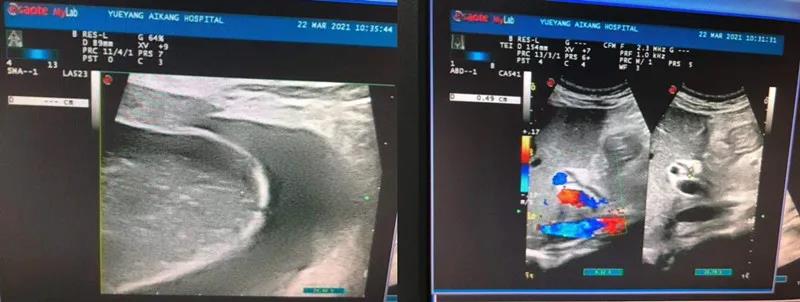

彩超檢查結(jié)果顯示:膽囊腫大、膽囊結(jié)石、急性膽囊炎

劉主任得知檢查結(jié)果后,迅速請普外科醫(yī)生會診。普外科周旭陽主任看到彩超結(jié)果單,提出需盡快手術(shù),否則隨時有穿孔的危險。而劉主任則擔心手術(shù)會發(fā)生產(chǎn)褥期感染,影響產(chǎn)后恢復(fù)。然而周主任的診療方案很快消除了劉主任的擔憂,張女士被迅速轉(zhuǎn)入普外科。